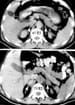

CT scan appearance is shown in the image below.

Computed tomography (CT) scans of the abdomen show normal adrenal glands several months before the onset of hemorrhage (upper panel) and enlarged adrenals 2 weeks after an acute episode of bilateral adrenal hemorrhage (lower panel). The attenuation of the adrenal glands, indicated by arrows, is increased after the acute event. Reproduced from Rao RH, Vagnucci AH, Amico JA: Bilateral massive adrenal hemorrhage: early recognition and treatment. Ann Intern Med. Feb 1 1989;110(3):227-35 with permission from the journal.